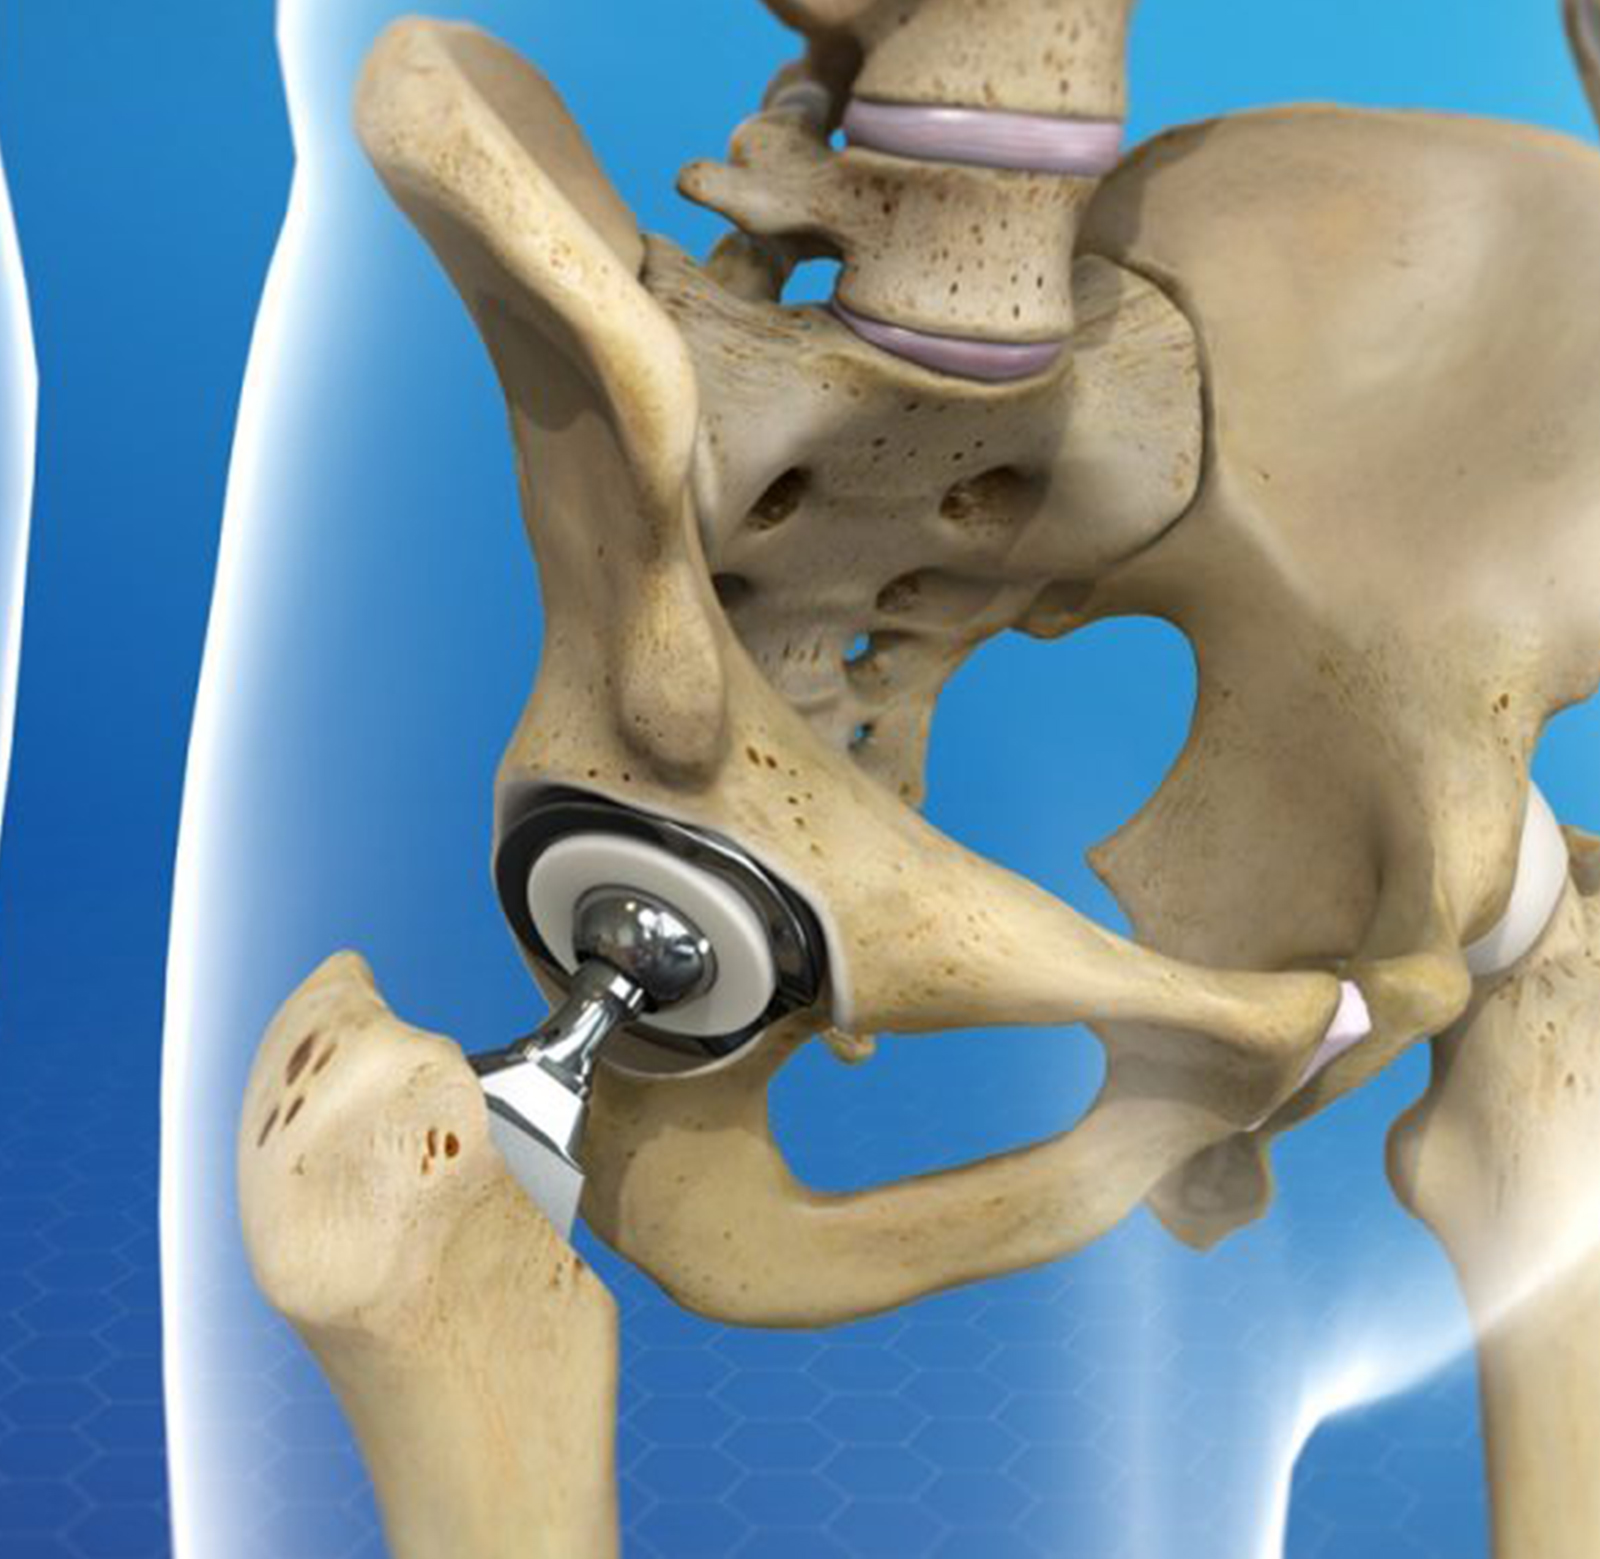

Замена таз сустава

Замена таз сустава 113 фотографий